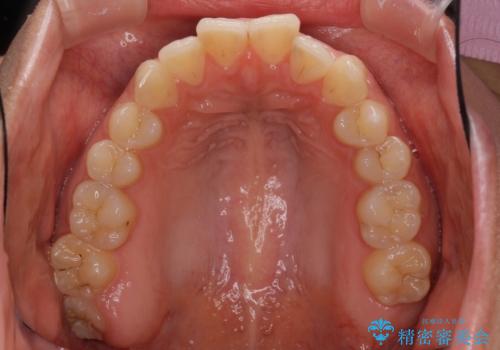

インビザライン矯正で前歯のデコボコを改善

- 前歯のデコボコを気にして来院された患者様です。

目立たないことを最優先にしたいとのことで、デコボコは軽度であったことから、インビザラインにて矯正治療を行うこととしました。

骨格的に下顎骨が左にずれており、上下の正中一致は困難ではありましたが、IPR(歯と歯の間を削る)や後方への移動など組み合わせて、できる限り改善しました。

インビザラインはマウスピースを外している時間が長いと、長期間使用しても前歯のデコボコはあまり改善されません。こちらの患者様は治療期間が長くなり、装着時間が短くなってしまったことで、気になる部分の改善により長期間を要するようになってしまいました。